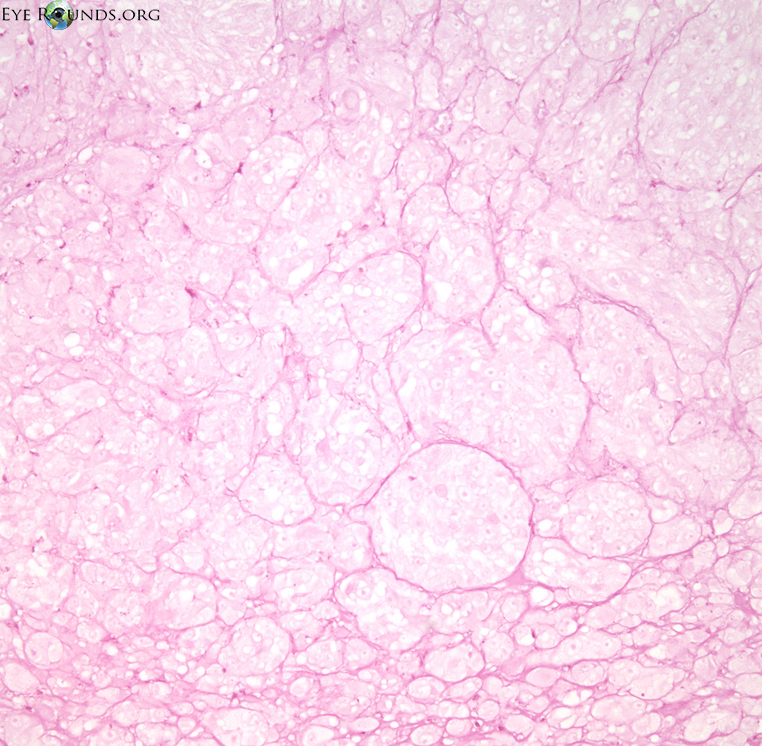

Figure 8: (click image for higher resolution)

Histolopathology demonstrating the choroidal melanoma which disrupts Bruch's membrane forming a "collar button" appearance

Histolopathology demonstrating the choroidal melanoma which disrupts Bruch's membrane forming a "collar button" appearance. An exudative retinal detachment is present adjacent to the tumor anteriorly. Hematoxylin and eosin, original magnification 10x

Histological diagnosis

Melanomas are classified based on histopathology as per the Modified Callender Classification, with a strong correlation between microscopic features and prognosis. Lesions can contain spindles cells, epitheloid cells, or both. Spindle cell melanomas have the best prognosis, epithelioid cell melanomas have the least favorable prognosis, and mixed-cell melanomas have an intermediate prognosis (9). Tumors made entirely of spindle A cells are nevi.